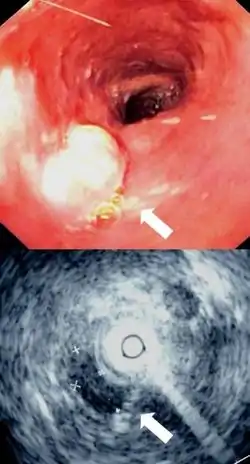

Additional testing is needed to assess how much the cancer has spread (see § Staging, below). Computed tomography (CT) of the chest, abdomen and pelvis can evaluate whether the cancer has spread to adjacent tissues or distant organs (especially liver and lymph nodes). The sensitivity of a CT scan is limited by its ability to detect masses (e.g. enlarged lymph nodes or involved organs) generally larger than 1 cm.[43][44] Positron emission tomography is also used to estimate the extent of the disease and is regarded as more precise than CT alone.[45] PET/MR as a novel modality has shown promising results in preoperative staging with fair feasibility and good correlation in comparison to PET/CT. It can enhance tissue differentiation with lowering the radiation dose to the patient.[46] Esophageal endoscopic ultrasound can provide staging information regarding the level of tumor invasion, and possible spread to regional lymph nodes.

Endoscopic image of Barrett esophagus – a frequent precursor of esophageal adenocarcinoma Endoscopy and radial endoscopic ultrasound images of a submucosal tumor in the central portion of the esophagus

Endoscopy and radial endoscopic ultrasound images of a submucosal tumor in the central portion of the esophagus Contrast CT scan showing an esophageal tumor (axial view)